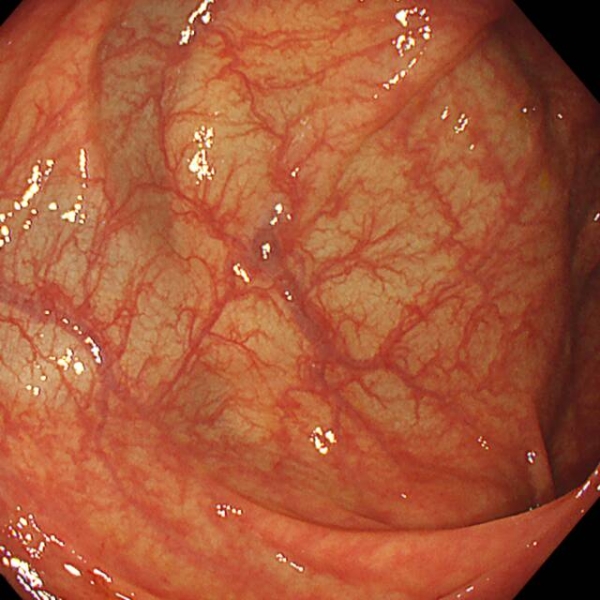

胃镜就像一台“高清摄像机”,医生通过它可以直接观察食管、胃和十二指肠的黏膜。医生关注的内容包括:

观察项目关注内容

黏膜颜色是否发红、发白

黏膜完整性是否有糜烂、溃疡、出血点

表面结构是否有隆起、凹陷

胃壁形态是否变薄、变脆、皱襞消失

分泌物是否有过多黏液、胆汁反流

血管纹理是否清晰可见

发现任何“可疑区域”,比如颜色异常、微小隆起等,医生都会取活检。